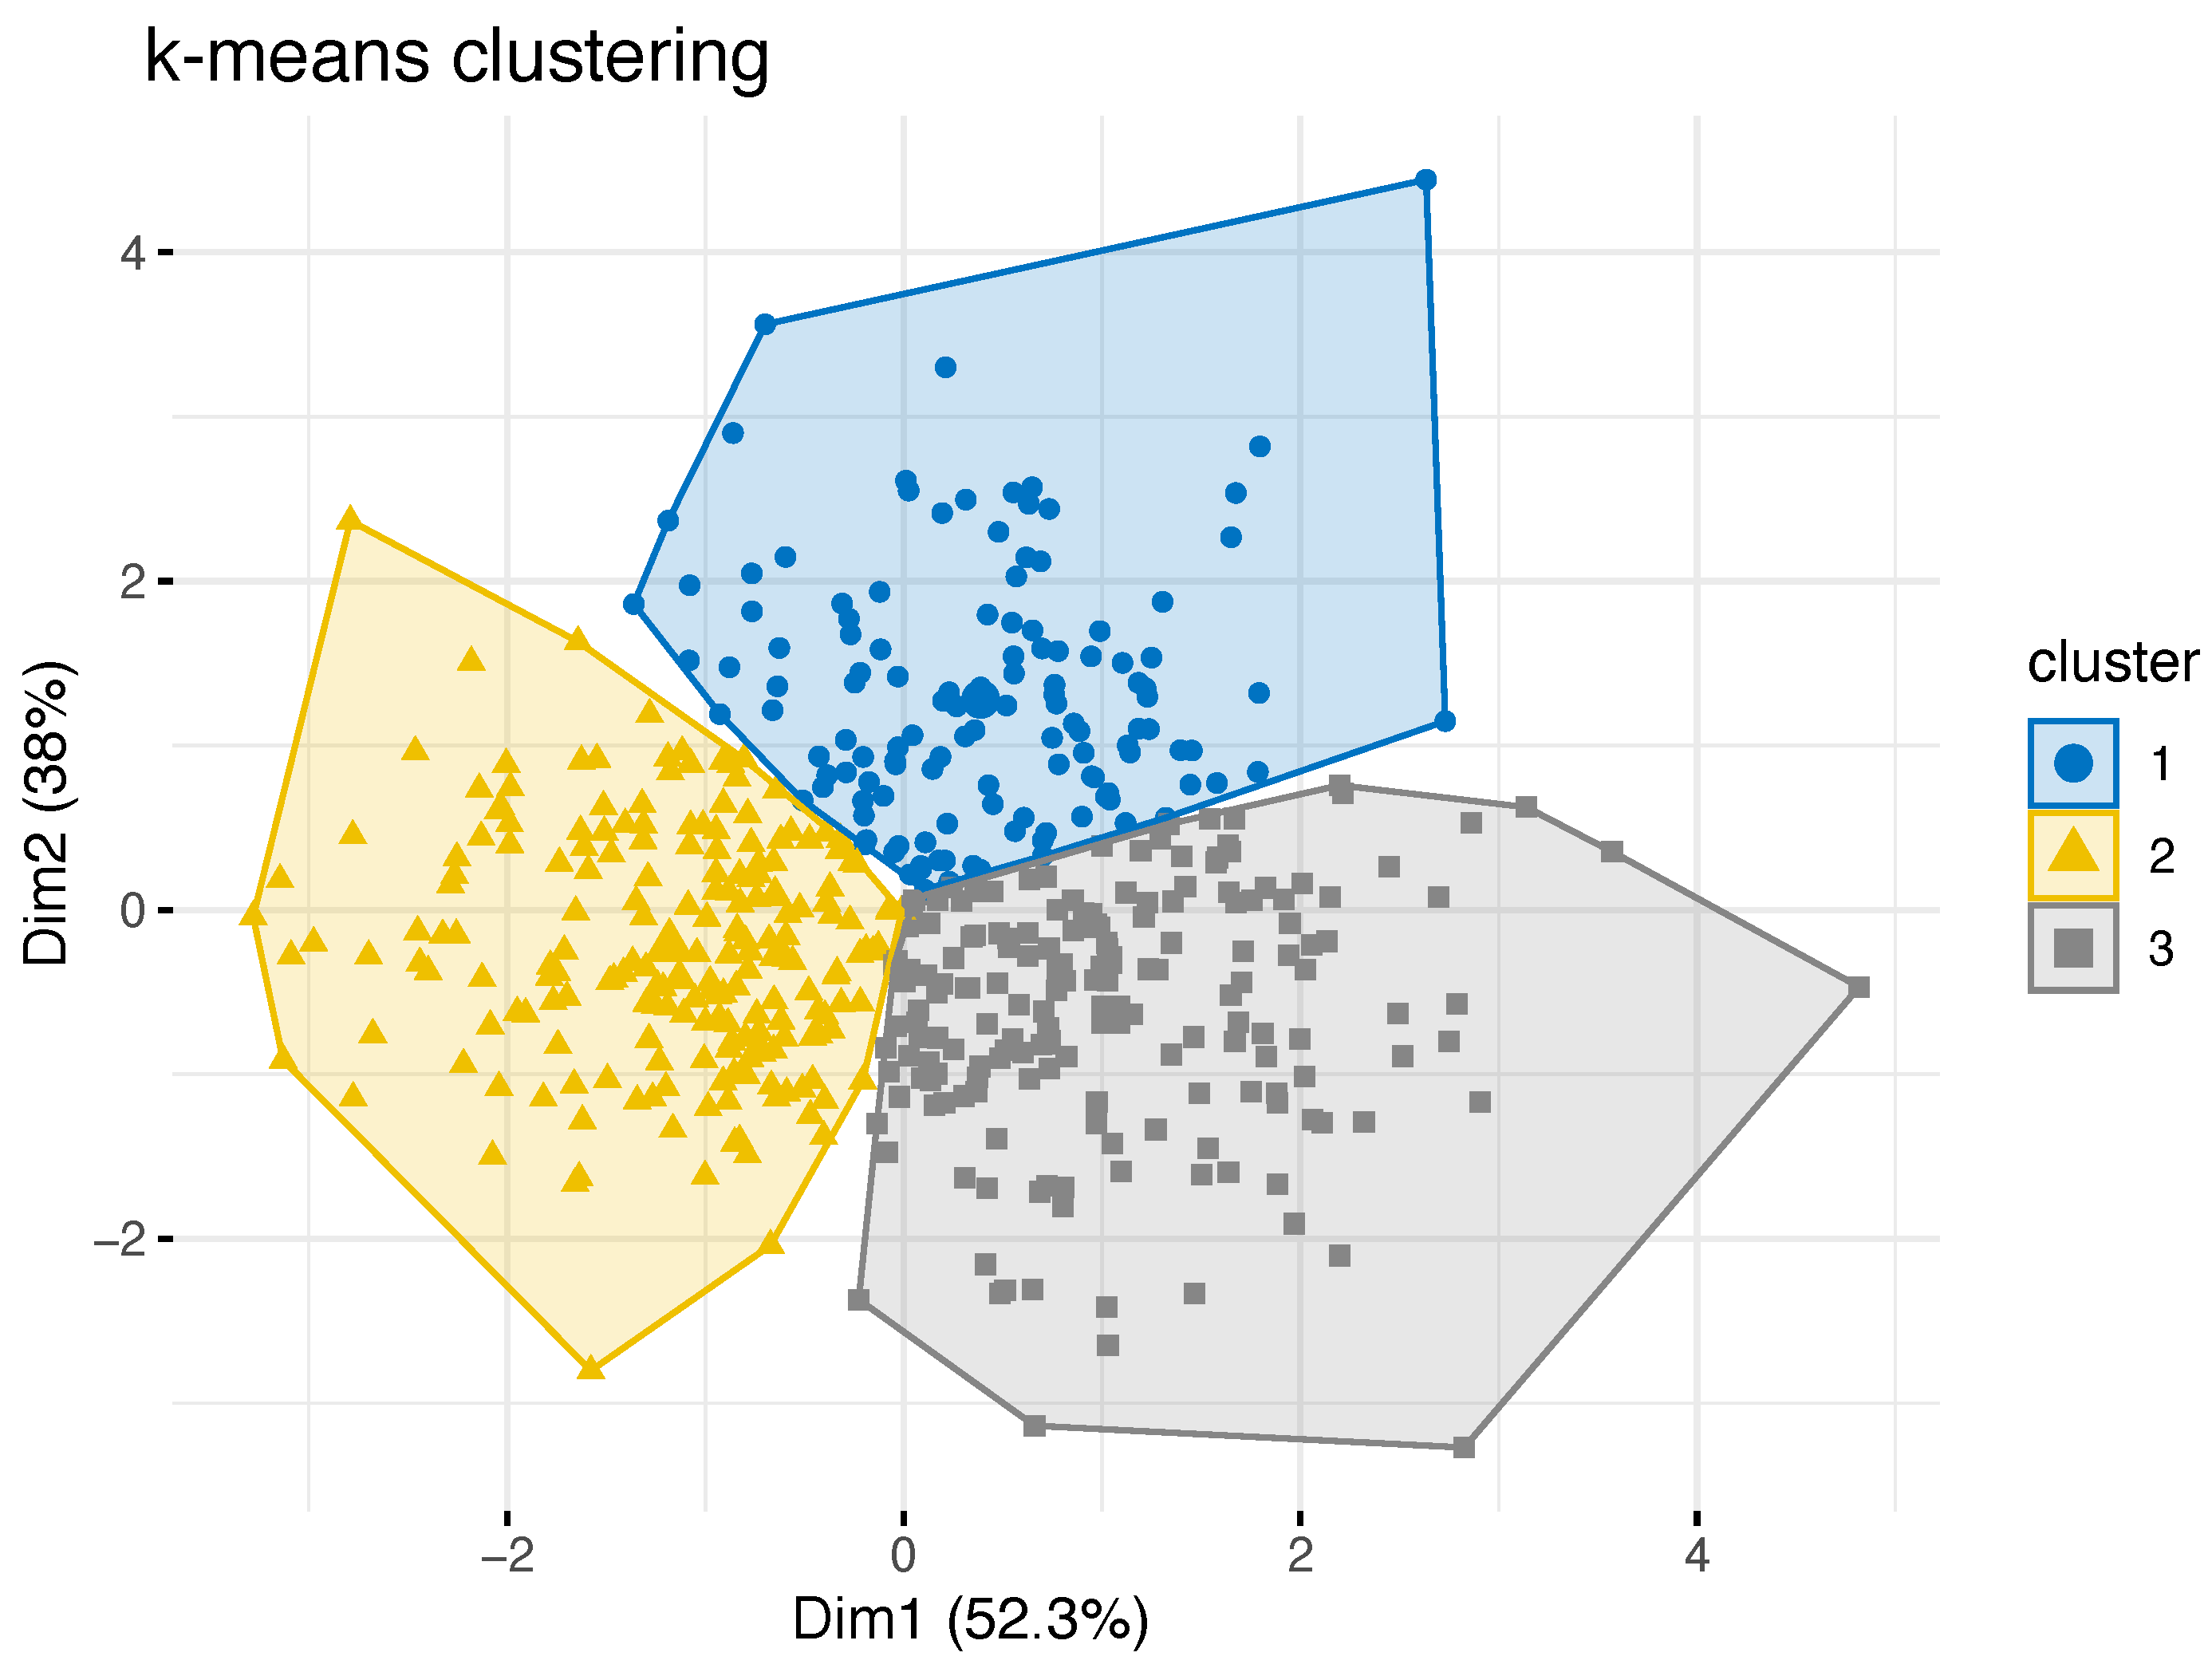

3.1. Cluster Identification

3.2. Cluster-Specific Skeletal Phenotypes

| Cluster 1 | Cluster 2 | Cluster 3 | p | ||||||||

|---|---|---|---|---|---|---|---|---|---|---|---|

| n | M | SD | n | M | SD | n | M | SD | |||

| age | 128 | 28.1 | 9.1 | 204 | 26.2 | 7.8 | 182 | 26.5 | 9.0 | n. s. | |

| female | 36 | 26.3 | 9.2 | 171 | 26.0 | 7.9 | 116 | 26.3 | 9.7 | n. s. | |

| male | 92 | 28.8 | 9.0 | 33 | 27.6 | 7.0 | 66 | 26.9 | 7.9 | n. s. | |

| 128 | 7.8 | 3.4 | 204 | 11.1 | 3.3 | 182 | 2.4 | 4.0 | <0.001 | ||

| AxV | 128 | 36.2 | 4.6 | 204 | 26.5 | 3.8 | 182 | 35.9 | 4.5 | <0.001 1 | |

| AxH | 128 | 98.9 | 5.5 | 204 | 88.1 | 5.4 | 182 | 85.6 | 5.6 | <0.001 | |

| Cluster | Skeletal Phenotype | AxV | AxH | |

|---|---|---|---|---|

| 1 | balanced face | 8 | 36 | 99 |

| 2 | vertical face, class II | 11 | 27 | 88 |

| 3 | horizontal face, class III | 2 | 36 | 86 |